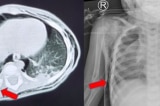

Uống nhầm tinh dầu đuổi muỗi, bé 15 tháng rơi vào nguy kịch, có nguy cơ xơ phổi

Bé trai 15 tháng tuổi được chuyển lên từ tuyến dưới, tiếp tục cấp cứu do uống nhầm tinh dầu đuổi muỗi. Hình ảnh chụp phổi cho thấy tổn thương lan tỏa hai bên, nguy…